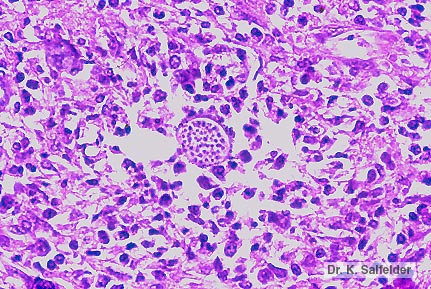

Abb. 9,24: Histoplasmose

Schnitt von einem Zellblock des Sputums. Die intrazellulaeren Histoplassmen sehen wie Endoaporen in einer reifen Sphaerule von Coccidioides immitis aus. HE-Faerbung